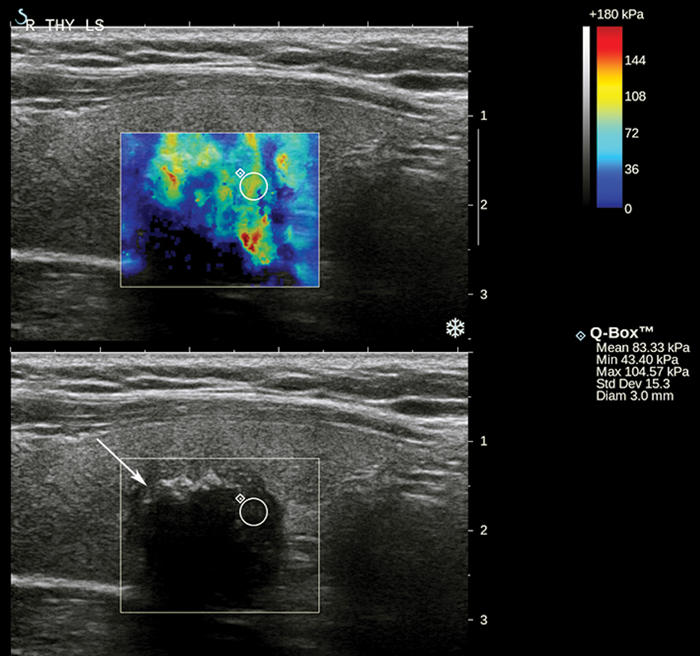

Thyroid ultrasound elastography: does nodule stiffness predict malignancy?

Approximately 50% of the general population has a thyroid nodule while 5-15% of these are malignant [1]. A major challenge, therefore, is how to detect the malignant nodules for appropriate, timely treatment and avoid unnecessary, costly investigations for the remainder....